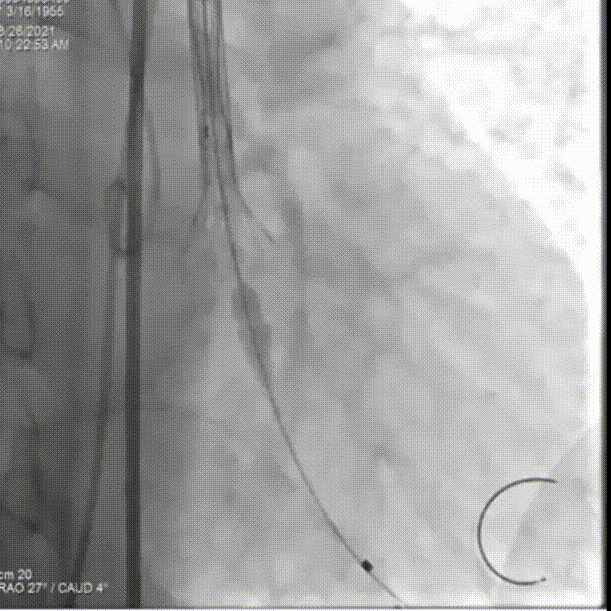

主动脉根部造影

球囊预扩

第一次尝试释放